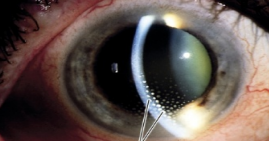

Double intrastromal corneal rings. Used for keratoconus.

Complications of surgery: Infection (Give TOPICAL antibiotic, not IV), corneal perforation, displacement,